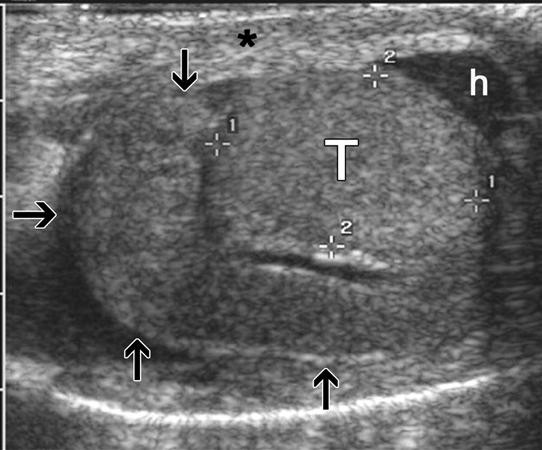

There are several features in the patient history that may indicate epididymitis, such as a history of previous sexually transmitted infections (STI), recent sexual activity, irritative voiding symptoms, BPH/incomplete emptying of the bladder, or UTI. The very sudden onset of pain and swelling is more typical of torsion, while a more gradual, progressive onset pain (often greater than 24 hours) suggests epididymitis. On physical examination, epididymitis presents with tenderness posterior and lateral to the testis (the usual location of the epididymis). Scrotal ultrasound may show an enlarged, hypervascular epididymis with normal or increased blood flow to the testis, which will distinguish this condition from torsion or trauma. Abscess formation within the epididymis or in the peri- epididymal tissues, can also be detected by ultrasound. The diagnostic challenge occurs when trying to distinguish advanced epididymoorchitis from late torsion. In both entities, there is typically a confluent mass in the scrotum with edema and fixation of the overlying scrotal wall that obliterate normal anatomic landmarks. Furthermore, advanced epididymoorchitis can result in testicular ischemia and infarction due to compression of the testicular vasculature from epididymal inflammation. On ultrasound, this may present in a very similar manner to testis torsion. In either case, the lack of testis blood flow on Doppler ultrasound requires surgical exploration which allows these conditions to be differentiated.

Ultrasound of epididymitis (arrows). (From Aso C, Goya Enríquez F: Gray-Scale and Color Doppler Sonography of Scrotal Disorders in Children: An Update. Radiographics. (2005) 25:1197-1214.)